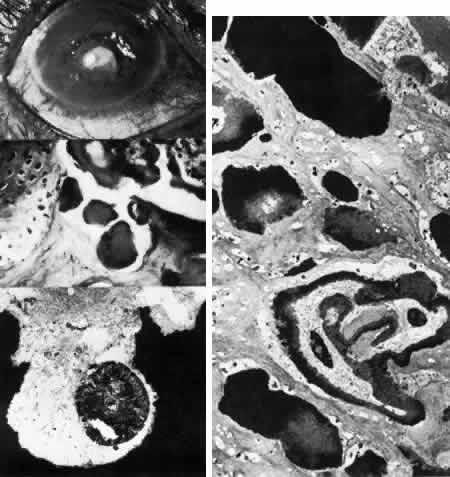

Sclerocornea

In sclerocornea (Fig. 4), the limbus is ill-defined since opaque scleral tissue with fine vascular conjunctival arcades extends into the peripheral cornea. A broad range of corneal involvement is possible, with the most extreme being complete sclerification of the cornea. Ninety percent of cases are bilateral, although generally asymmetric. Most cases are sporadic; there is no known heredity. Sclerocornea is nonprogressive and must be differentiated from interstitial inflammatory conditions and arcus juvenilis (congenital peripheral lipid deposition, also known as anterior embryotoxon). Sclerocornea is associated with cornea plana in approximately 80% of cases.44 Other associated ocular abnormalities include microphthalmos, iridocorneal synechiae, persistent pupillary membrane, dysgenesis of angle and iris, congenital glaucoma, colobomas, and posterior embryotoxon of the fellow eye.45 Somatic abnormalities sometimes occur along with associated chromosomal abnormalities; they include mental retardation, deafness, and craniofacial, digital and skin abnormalities.44

Fig. 4. Sclerocornea. Schematic drawing of ocular features Top left. In a minimally affected patient with additional findings of ptosis, strabismus, and hearing loss, only the peripheral cornea is opacified. Top center. In this advanced case with chromosomal translocation and multiple congenital abnormalities, the entire cornea is sclerified and the fine vascular arcades extend centrally from the conjunctiva and sclera. Top right. Light micrograph of anterior cornea shows edematous disorganization of epithelium, fragmentation of Bowman's membrane (B), and interstitial vascularization (V) (hematoxylin-eosin, × 200). Middle left. Transmission electron micrograph of normal human corneal stroma is shown for comparative purposes. Note uniform 240- to 260-nm collagen fibril diameter (× 50,000). Middle right. Transmission electron micrograph of sclerocornea at same magnification shows disorganized array of collagen fibrils that measure as much as three times normal diameter (× 50,000). Bottom. Transmission electron micrograph of posterior cornea shows abnormal Descemet's membrane of less than 1μm thickness (DM, bracketed) and attenuated endothelial cells (× 10,500). (Schematic. Grayson M: Diseases of the Cornea, p 32. St. Louis, CV Mosby, 1979; Top center and right. Rodrigues MM, Calhoun J, Weinreb S: Sclerocornea with an unbalanced translocation [17p, 10q]. Am J Ophthalmol 78:49, 1974)

Ultrastructural studies22,46,47 have shown the involved stroma to assume the morphologic features of scleral tissue, with irregularly arranged collagen fibrils of variable and immensely enlarged diameter for corneal tissue (up to 150 nm, comparable to normal scleral collagen). The precise lamellar organization of normal corneal stroma is not present; thus optical clarity is not achieved. Various abnormalities of endothelium and Descemet's membrane exist, from attenuation to focal absence. Descemet's membrane is generally thin, with multilaminar deposition of basement membrane-like collagen.

Pathophysiologically, sclerocornea may result from developmental arrest of limbal differentiation during neural crest migration, as occurs with the other mesenchymal dysgeneses.22